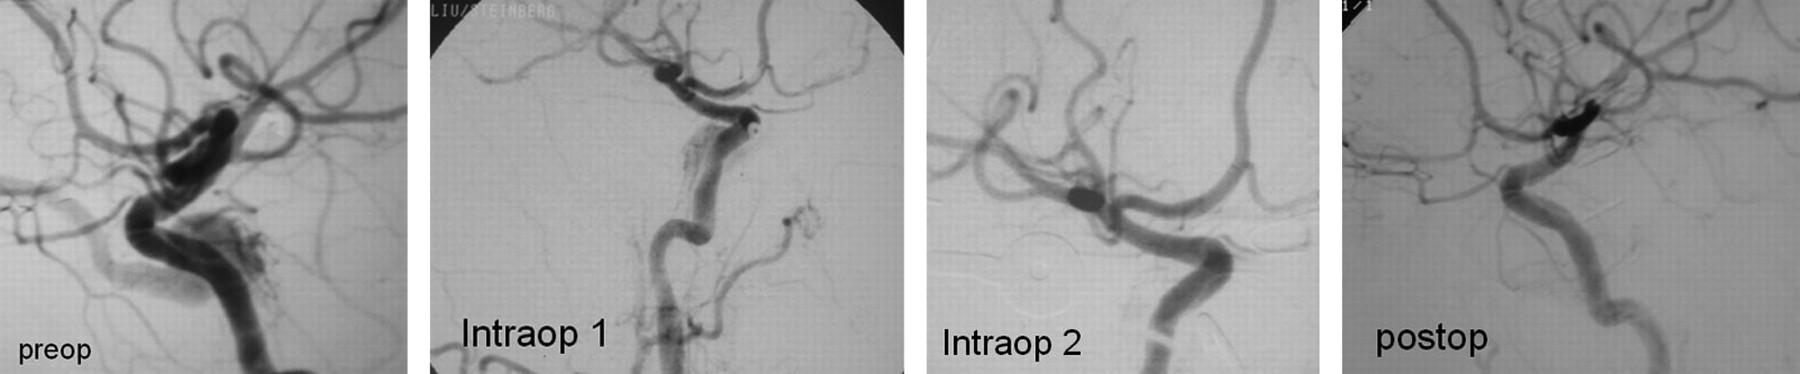

Preoperative left ICA injection, lateral projection showing a CCF. Following an unsuccessful attempt at endovascular treatment, it was treated surgically. The first IA shows evidence of residual fistula, after which the surgeon further packed the cavernous sinus. The second intraoperative angiogram and a postoperative angiogram show no evidence of residual fistula.